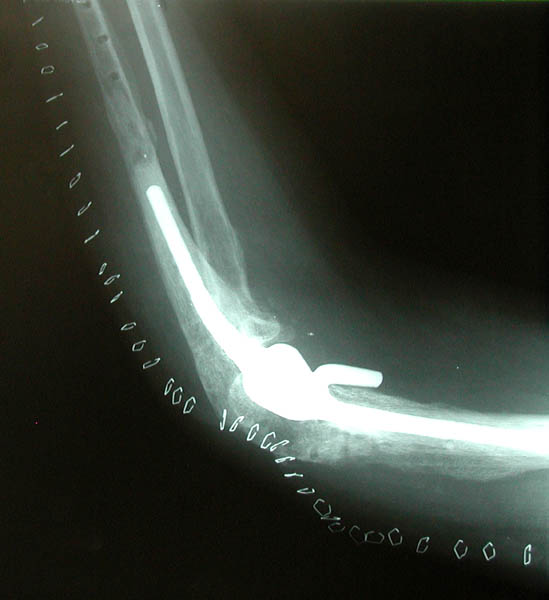

Side and front views of Marla's new artificial elbow joint! You can see the staples that hold the surgical incision closed.